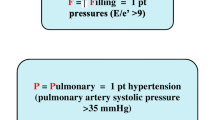

Risk stratification

Cardiac imaging, in conjunction with clinical indices, has the potential to more precisely risk stratify patients. Shah et al. [24] identified three distinct HFpEF clinical phenotypes with markedly differing prognosis. The first group, which was relatively young (mean age 61 years) and had comparatively low natriuretic peptide levels (median brain natriuretic peptide (BNP) 72 pg/mL) and normal or only mildly abnormal diastolic function, had the best prognosis. The second group had features in keeping with what has previously been described as ‘metabolic HF’, or more recently, the ‘HFpEF obesity phenotype’, with a high prevalence of obesity, diabetes and obstructive sleep apnoea [3, 73]. Diastolic dysfunction (three-quarters had moderate or severe dysfunction), LA dilatation and LV hypertrophy were prominent and right atrial pressure was also relatively high, thought to reflect pericardial constraint, possibly by epicardial adipose tissue. The unadjusted HR for death in this group, in comparison with the first group, was 4.0 [confidence interval: 1.5–10.9]. After adjusting for BNP and the Meta-Analysis Global Group in Chronic Heart Failure (MAGGIC) risk score, the HR for death was 2.2 [confidence interval: 0.8–6.0], which was highest of all of the groups. The third group had the highest prevalence of hypertension and AF and demonstrated the largest LA volumes, highest LV mass, highest BNP levels and most severe diastolic dysfunction. Patients were also more likely to have pulmonary hypertension and right heart dysfunction. In comparison with the first group, the third group had an unadjusted HR for death of 6.5 [confidence interval: 2.5–16.6].